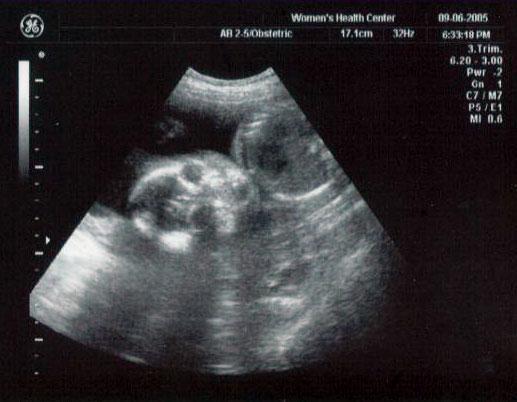

24 week ultrasound ~ All scrunched up in there!

24 week ultrasound ~ Our little alien caught in mid-yawn! (Tilt your head to the left if you need to...)